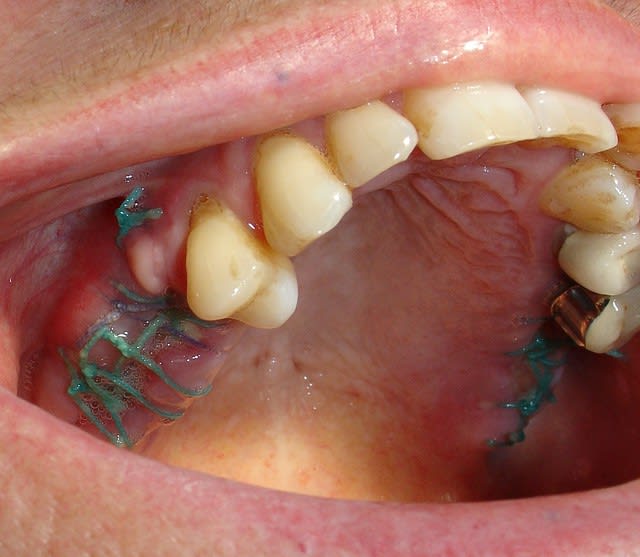

La suite des extractions et comblement par matri bone Prf.

Résultat rx et visuel à 8 jours.

Pour le moment rien que du très classique.